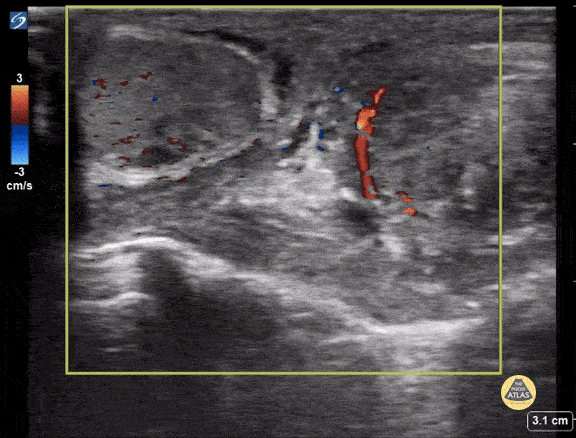

Peds-Genitourinary - Left Sided Testicular Torsion

15 yo M with sudden onset testicular pain (left) and vomiting. POCUS shows decreased flow to the left testicle consistent with torsion. he was taken immediately to the OR. Contributor: Kathryn Pade, MD, Rady Children's Hospital San Diego